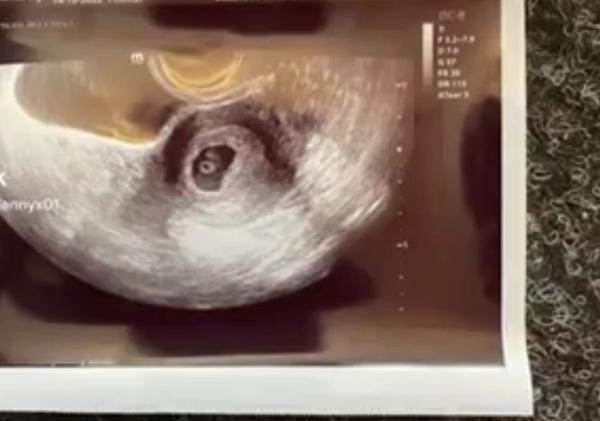

Dle UZ 6+4, dokonce jsem slyšela i ❤️🥰 6 mm

Myslíte si, ze to termínu odpovídá? Překládám i foto.